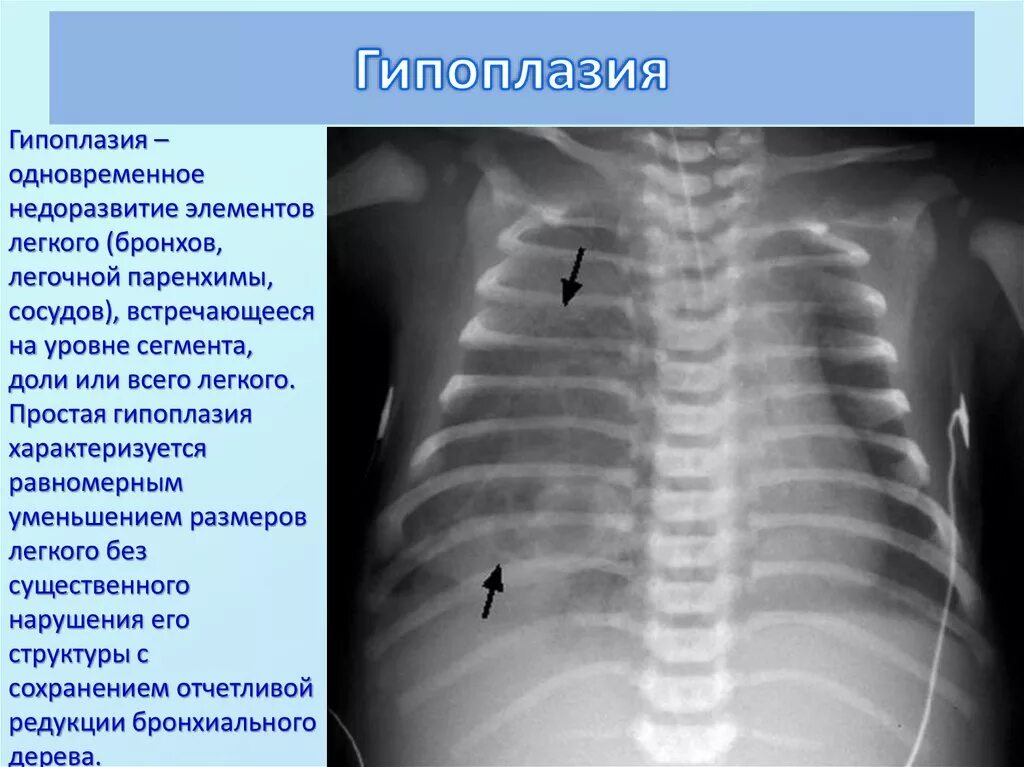

Гипоплазия 12 пары ребер